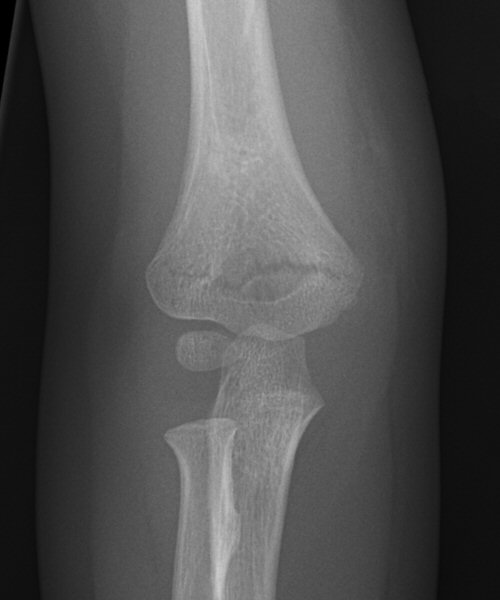

Suprakondylär humerusfraktur, Gartland 1.2, Rogers line delar capitulum radii, behandlades icke-kirurgiskt